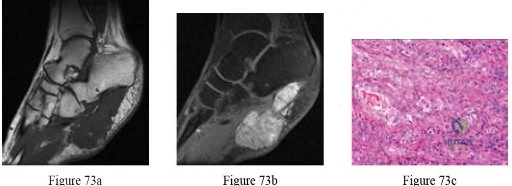

Question 73

Non-steroidal anti-inflammatory drugs (NSAIDs) are frequently withheld in the acute post-operative period following fracture fixation due to concerns regarding impaired bone healing. NSAIDs primarily inhibit fracture healing by directly suppressing which of the following processes?

Explanation